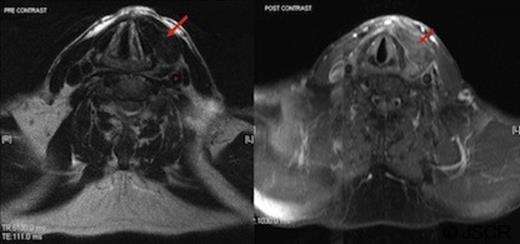

Intravenous gadolinium contrast demonstrated peripheral enhancement of the mass (Figure.3); given the history and preceding cardioversion it was felt the most likely diagnosis was that of a haematoma.

MRI imaging (pre then post contrast) demonstrates enhancement of the left sided mass with gadolinium (arrow); suggesting the presence of blood. The carotid sheath (*) can be seen separately from the mass and is marginally displaced posteriorly.